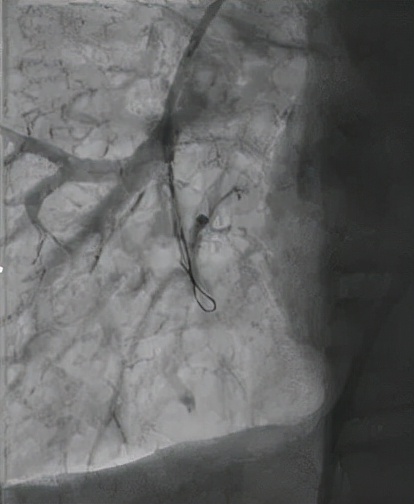

△導絲進入狹窄的肺動脈造影,明確病變血管

△送入OCT(光學相干斷層成像)導管進行血管掃描,明確血管病變為網格樣的慢性血栓